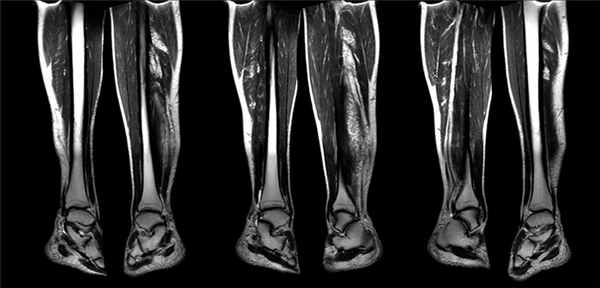

МРТ нижних конечностей

Высокая результативность МРТ нижних конечностей обеспечивается благодаря послойному сканированию тканей в разных проекциях. Процедура помогает обнаружить патологические изменения на ранних стадиях еще до появления симптомов, а также уточнить диагноз при неоднозначных результатах предыдущей диагностики.

Магнитно-резонансную томографию могут назначить при жалобах пациента на онемение ног, изменение цвета кожи, ощущение неуправляемости и снижение мышечной активности нижних конечностей. Выяснить, что спровоцировало неприятную симптоматику, помогают разные методы диагностики. Давно испытанные и доступные по стоимости УЗИ, рентген и КТ не раз доказали свою эффективность, но они не всегда дают полную и ясную картину состояния тканей. В таких случаях врачи рекомендуют сделать МРТ. Метод, основанный на способности магнитного поля выстраивать атомы водорода в заданной последовательности, позволяет визуализировать костные и мягкие ткани таза, бедра, голени и стопы.